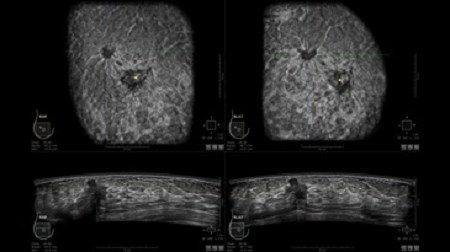

GE INVENIA ABUS – это современный УЗИ аппарат, который создан для точной и эффективной диагностики сканирования с высокой плотностью молочных желез. Выявляемость патологий раковых и предраковых стадий заболевания составляет 55%, что в конечном счете позволяет ставить врачу точные и своевременные диагнозы. Традиционные методы использования маммографии не показывают такой выявляемости, ограничиваясь лишь 3-38%.

УЗИ-аппарат GE INVENIA ABUS позволяет проводить максимально операторонезависимые процедуры, что значительно снижает риск неправильной постановки диагноза и сопутствующие издержки на обработку информации. Система готовит отчет в течение 3-х минут после сканирования, это безусловное преимущество по сравнению с обычным УЗИ сканером.

• Получение объемных 3D изображений с возможностью покадрового просмотра

• Получение изображений в поперечной плоскости (в реальном времени) и в коронарной плоскости (статическая, для указания нахождения соска)

• Отображение объемных 3D ультразвуковых изображений, которые состоят из традиционных поперечных и воссозданных коронарных и сагиттальных проекций

• Стандартизованная ориентация изображения: «толстый срез» в коронарной плоскости; поперечная; сагиттальная плоскость; радиальный и антирадиальный поворот изображения; просмотр исключительно области интереса

• Одновременный просмотр двух изображений для сопоставления в коронарной плоскости